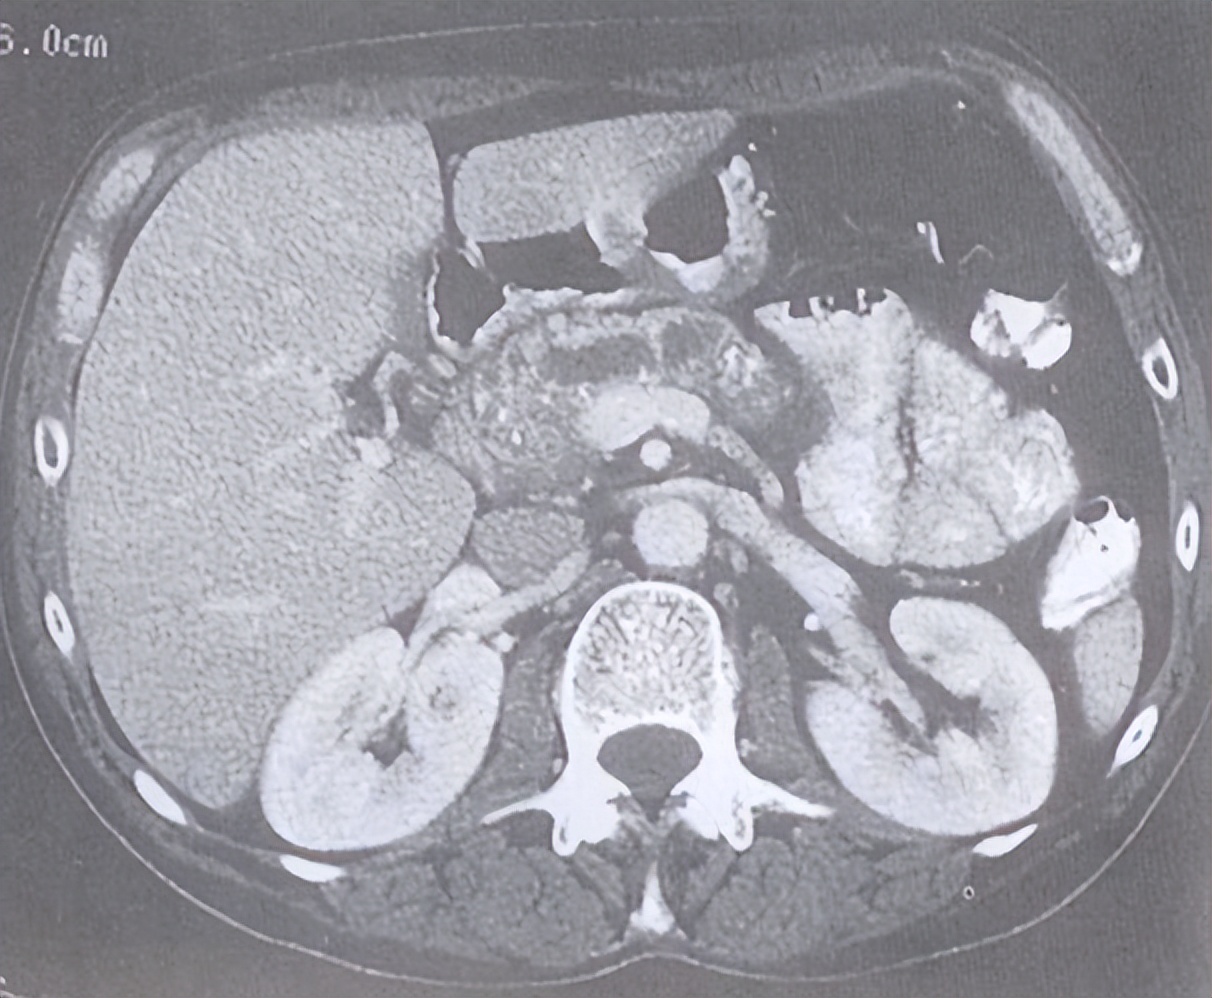

这是接受ERCP治疗最多的病种。肝外胆管结石要尽早取掉,因为胆管是每天1000ml胆汁流到肠道的唯一通道,而结石相当于江河中的巨石,一旦结石堵塞胆管,胆汁将无法下行而倒流入血,可能会出现:腹痛、发热、黄疸,严重者出现休克及神经精神症状甚至死亡。

1)急性胆源性胰腺炎:是胆道结石引发的急性胰腺炎,占急性胰腺炎的50%-60%。通过ERCP将胆道疾病解决后胰腺炎自然能逐步缓解。